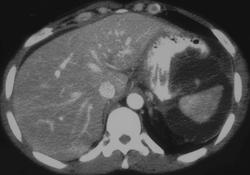

CASE NUMBER 2

Pancreatic Abscess